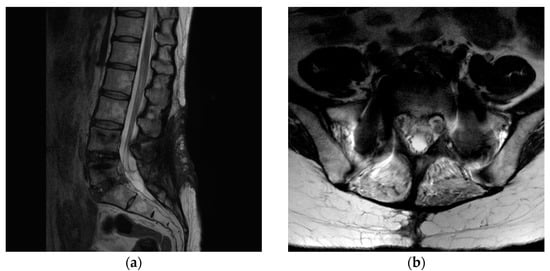

A 43-year-old woman presented to our hospital with a radiating pain in her left lower extremity. The visual analogue scale (VAS) score in her legs was 9. Magnetic resonance imaging (MRI) showed an L5/S1-level left central herniated disc. Computed tomography (CT) revealed combined posterior ring apophysis fracture at the same level (Figure 1). Conservative management did not work; therefore, she underwent microscopic discectomy. Postoperatively, she was discharged uneventfully, with improvements in the radiating pain.

Figure 1.

A 43-year-old woman presented with a radiating pain in her left lower extremity. (a) Magnetic resonance imaging (MRI) showed left central herniated disc at the L5/S1 level. (b) Computed tomography (CT) revealed a combined posterior ring apophysis fracture at the same level.